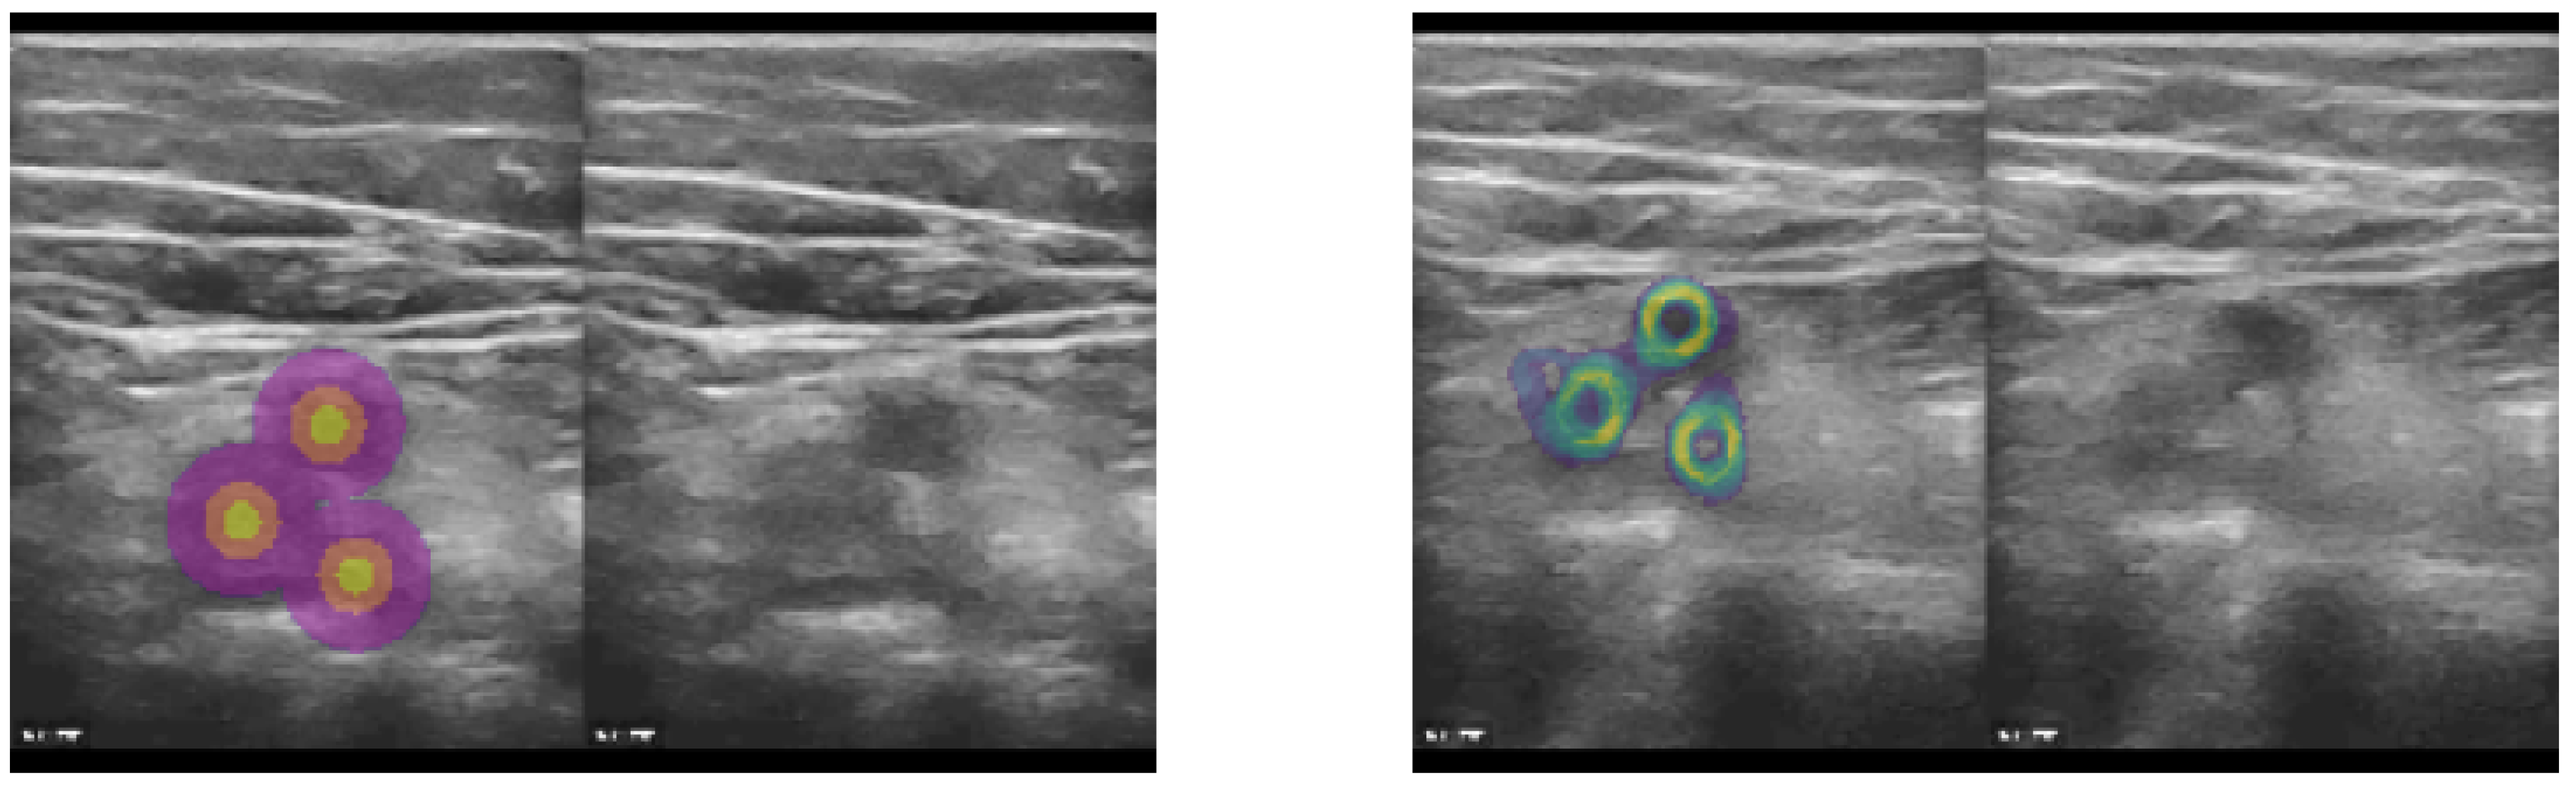

2.1.3. Sparse Supervision

Figure 3. The concept was to employ sparse landmarks as spatial transformer (warping) loss by generating pseudo segmentation labels that could be directly used in affine augmentation and Dice loss functions. Based on either segmentation centroids or manual landmark coordinates (here vessel centres), we generated three concentric circles (heatmap labels) that defined the precise location, as well as a robust neighourhood of each landmark, for improved supervision. Left: Heatmap labels, along with original CoCoAI frame. Right: Tenth temporal frame in sequence with overlay of all warped heatmaps (middle label) averaged. It can be seen that the motion was very well compensated and only minimal deviations of the warped labels from their ground truth locations was visible.